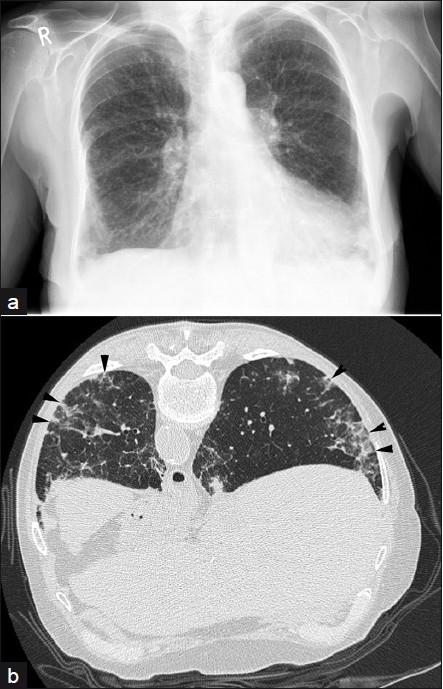

Drug induced lung disease

- Methotrexate induced acute interstitial pneumonitis

- 1-5% of patients

- subacute, progressive cough, dyspnea and fever

- CXR:

- diffuse bilateral, basal interstitial or alveolar infiltrate

- LA or pleural effusions may suggest this diagnosis

- CT:

- NSIP pattern

Methotrexate induced lung disease